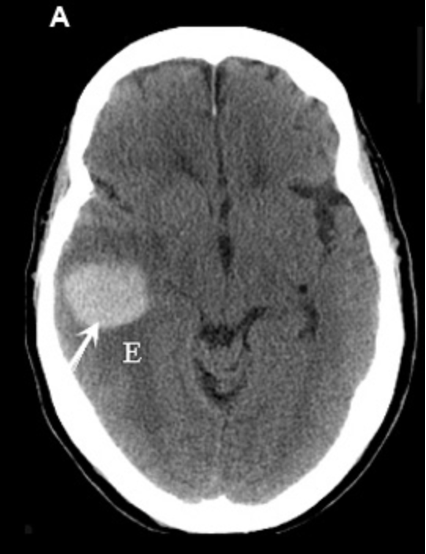

Q

Diagnose?

A

Subarachnoidalblødning (SAH)

Intracerebral hæmoragi (ICH)